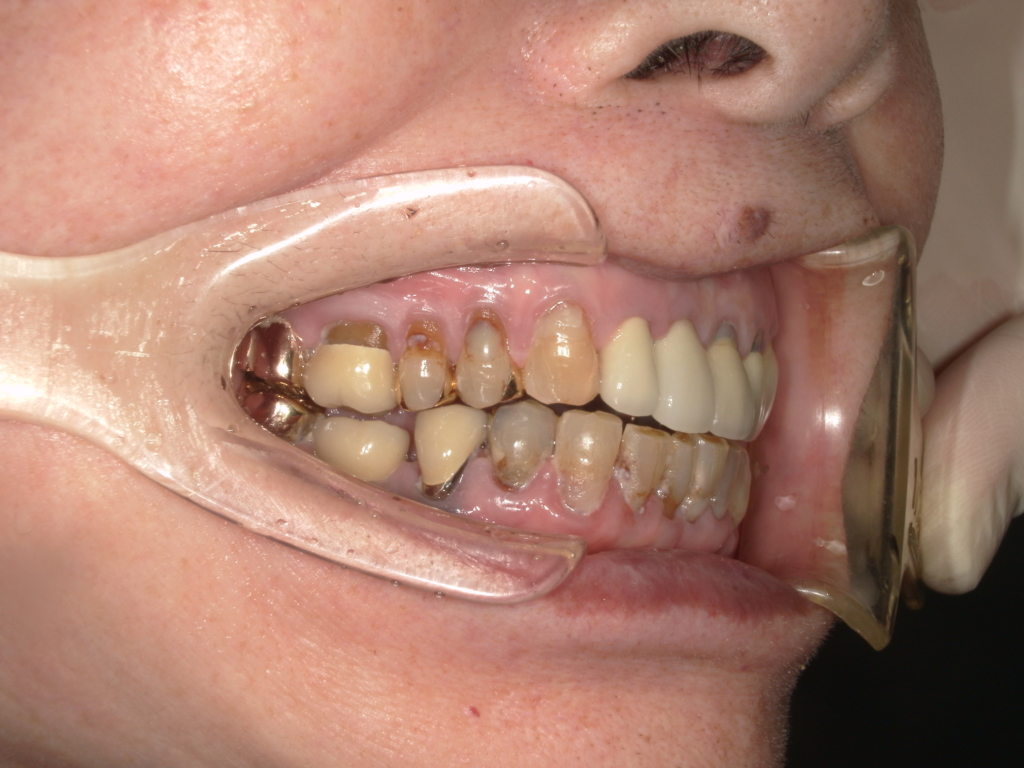

Y様インプラント実例 #44

左の上下の奥歯をインプラントで治療しています。

左下の奥歯は歯を抜くのと同時にインプラントの埋め込みを行っています。

被せものは上下、セラミックスで作っています。

治療前

治療後